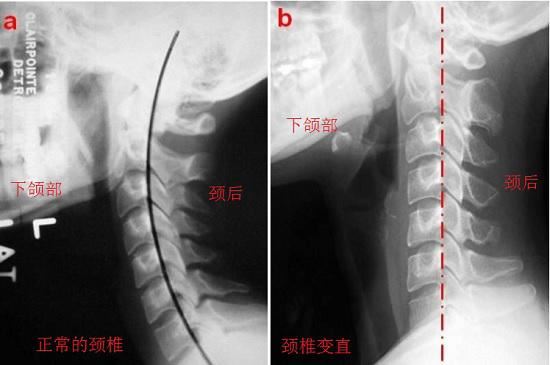

颈椎的生理曲度变化